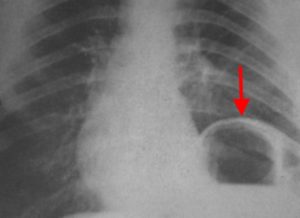

- Лучевая диагностика. Рентгенография и КТ грудной клетки являются наиболее информативными методами исследования диафрагмы. На рентгенограмме визуализируется высокое расположение одного из куполов (уровень II–V ребра). При рентгеноскопии обнаруживается парадоксальное движение диафрагмального свода. Использование контраста позволяет выявить перегибы пищевода, желудка, смещение органов пищеварения кверху. КТ наиболее точно определяет степень релаксации, помогает распознать вторичную патологию внутренних органов.

При релаксации диафрагма человека имеет верный, непрерывный, дугообразный контур. Все органы брюшной полости размещаются под мембраной, на стенах кишки и желудка отсутствуют втяжения. При релаксации рентгенологическая картина характеризуется всепостоянством.

Пограничная грудобрюшная линия может быть образована как диафрагмальной перегородкой, так и большой кривизной желудка, обращенной краниально. Диагноз релаксации диафрагмы несомненен, если контуры диафрагмальной перегородки и контуры желудка четко отделимы.

Если верхние контуры желудка и толстой кишки расположены на разных уровнях и между ними не прослеживается полоса диафрагмы, диагноз грыжи более вероятен, особенно когда при положений тела головой вниз высота расположения органов меняется различно. При релаксации отношения более постоянны.

Если виден один контур, то, уменьшая количество воздуха в желудке, можно либо отделить его стенку от диафрагмы, либо установить, что изломанная пограничная линия образована желудком. Повторные рентгенологические исследования показывают относительное постоянство картины при релаксации и большую изменчивость при грыже.